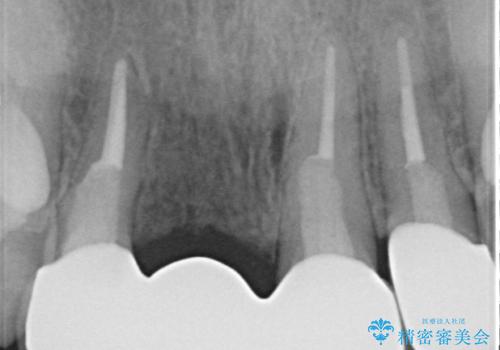

- 右上の前歯が折れてしまったので診て欲しいといらっしゃった方の症例です。

右上1番目の歯は保存不可能だったため抜歯し、ブリッジによる補綴を行いました。

- 根管治療により痛みや腫れがひかない事や、術後に痛みや腫れが生じる事、治療によるファイル破折やパーフォレーションなどの偶発症、術後の歯根破折を生じる可能性もあります